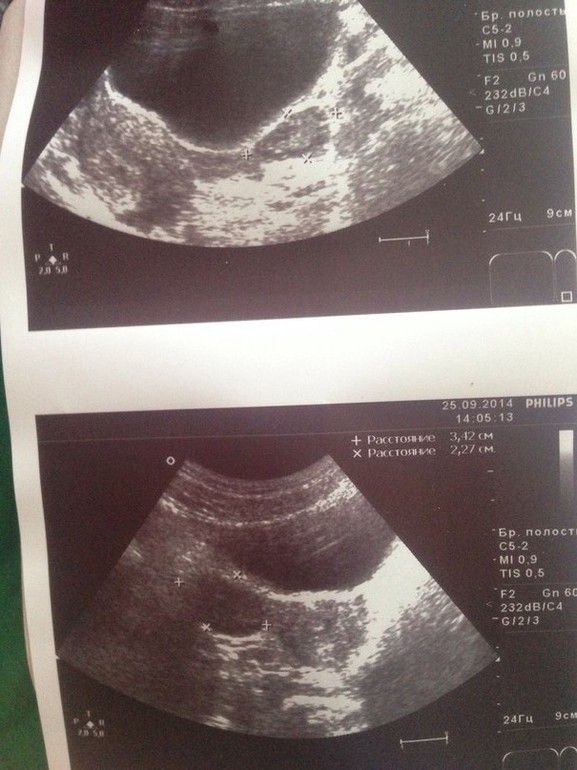

Ждем дня Х (Признаки беременности / Тесты)Девочки всем добрый день)) Мы с парнем очень хотим малыша, но у нас такая ситуация, мне 20 лет, два с половиной года стояла спираль(беременности и абортов у меня не было) спираль стояла хорошо, жалоб не было, когда решили что хотим малыша я ее вытащила в конце июля, с 4 сентября начали стараться(с того момента как закончились месячные) недавно были на узи, врач сказал что у меня начало овуляцие, хотя делала тест на овуляцию результат отрицательный, он мне дал этот снимок девочки кто что скажет, очень хочу забеременеть.

Я не врач-узист,не умею читать снимки,но там что то такое огромное может ко врачу сходит!?

А размеры фолликулов сказал? Толщину эндометрия? Снимки мало кто поймет)

Овуляция значит уже была. Врач странный раз сказал о ней. Про желтое тело говорил что нибудь? И тест раньше покажет беременность, чем узи. Сдайте лучше кровь на хгч.

Сказал что Овуляцию, про миому не чего не говорил, говорил что у меня слабенькое восполение правого придатка, что Узист что Гинеколог сказал что я здорова